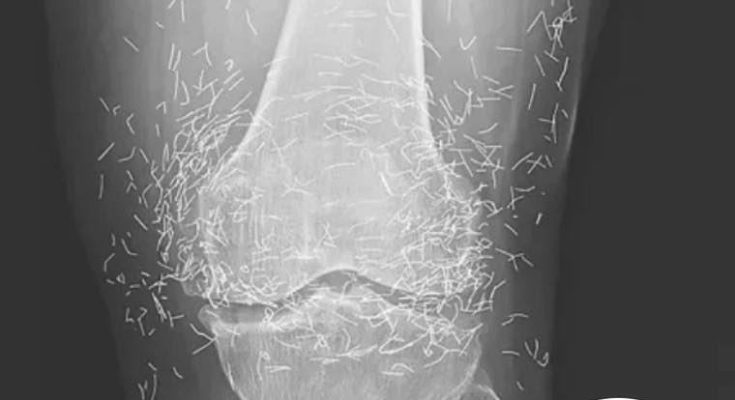

A 65-year-old woman in South Korea experienced a shocking medical discovery when doctors found hundreds of tiny gold needles embedded in her knee tissue during a routine X-ray. She had been suffering from chronic osteoarthritis, a condition that causes joint pain, stiffness, and inflammation due to cartilage breakdown.

In this case, the needles were intentionally left in her body as part of a long-term treatment strategy. Some practitioners believe that leaving gold needles or threads in place can provide ongoing stimulation to the affected area. However, medical professionals warn that this approach carries significant risks.

Dr. Ali Guermazi, a radiology expert from Boston University not involved in the case, explained that the human body can react negatively to foreign objects. Inflammatory responses, tissue damage, and infections are potential complications. Additionally, the embedded needles can interfere with medical imaging, making diagnosis more difficult.